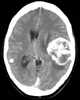

Metastasis from leiomyosarcoma

Leiomyosarcoma, is a malignant (cancerous) smooth muscle tumor. A benign tumor originating from the same tissue is termed leiomyoma. [Source: Wikipedia ]